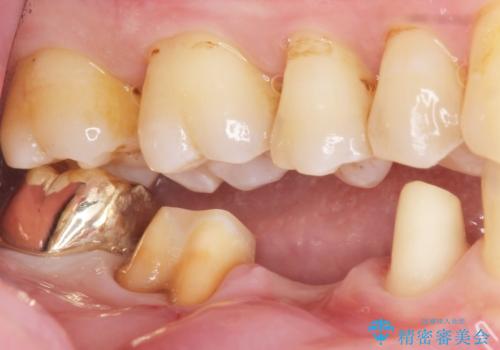

- 右下の奥歯がしみることを主訴に来院された患者様です。

精査したところ、横向きに生えた親知らずのせいで隣の歯(右下7)が虫歯になっていました。

親知らずを抜歯して隣の歯のう蝕を除去し、歯肉の治癒をしっかり待ったのち、患者様のご希望によりゴールド(PGA)クラウンによる補綴を行いました。